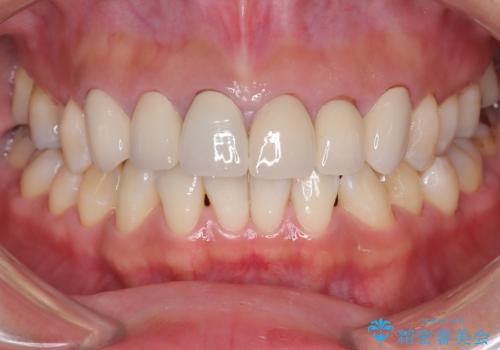

前歯の突出を防ぎながらガタつきを解消。上下左右4番抜歯による審美ワイヤー矯正

担当医 河口智英